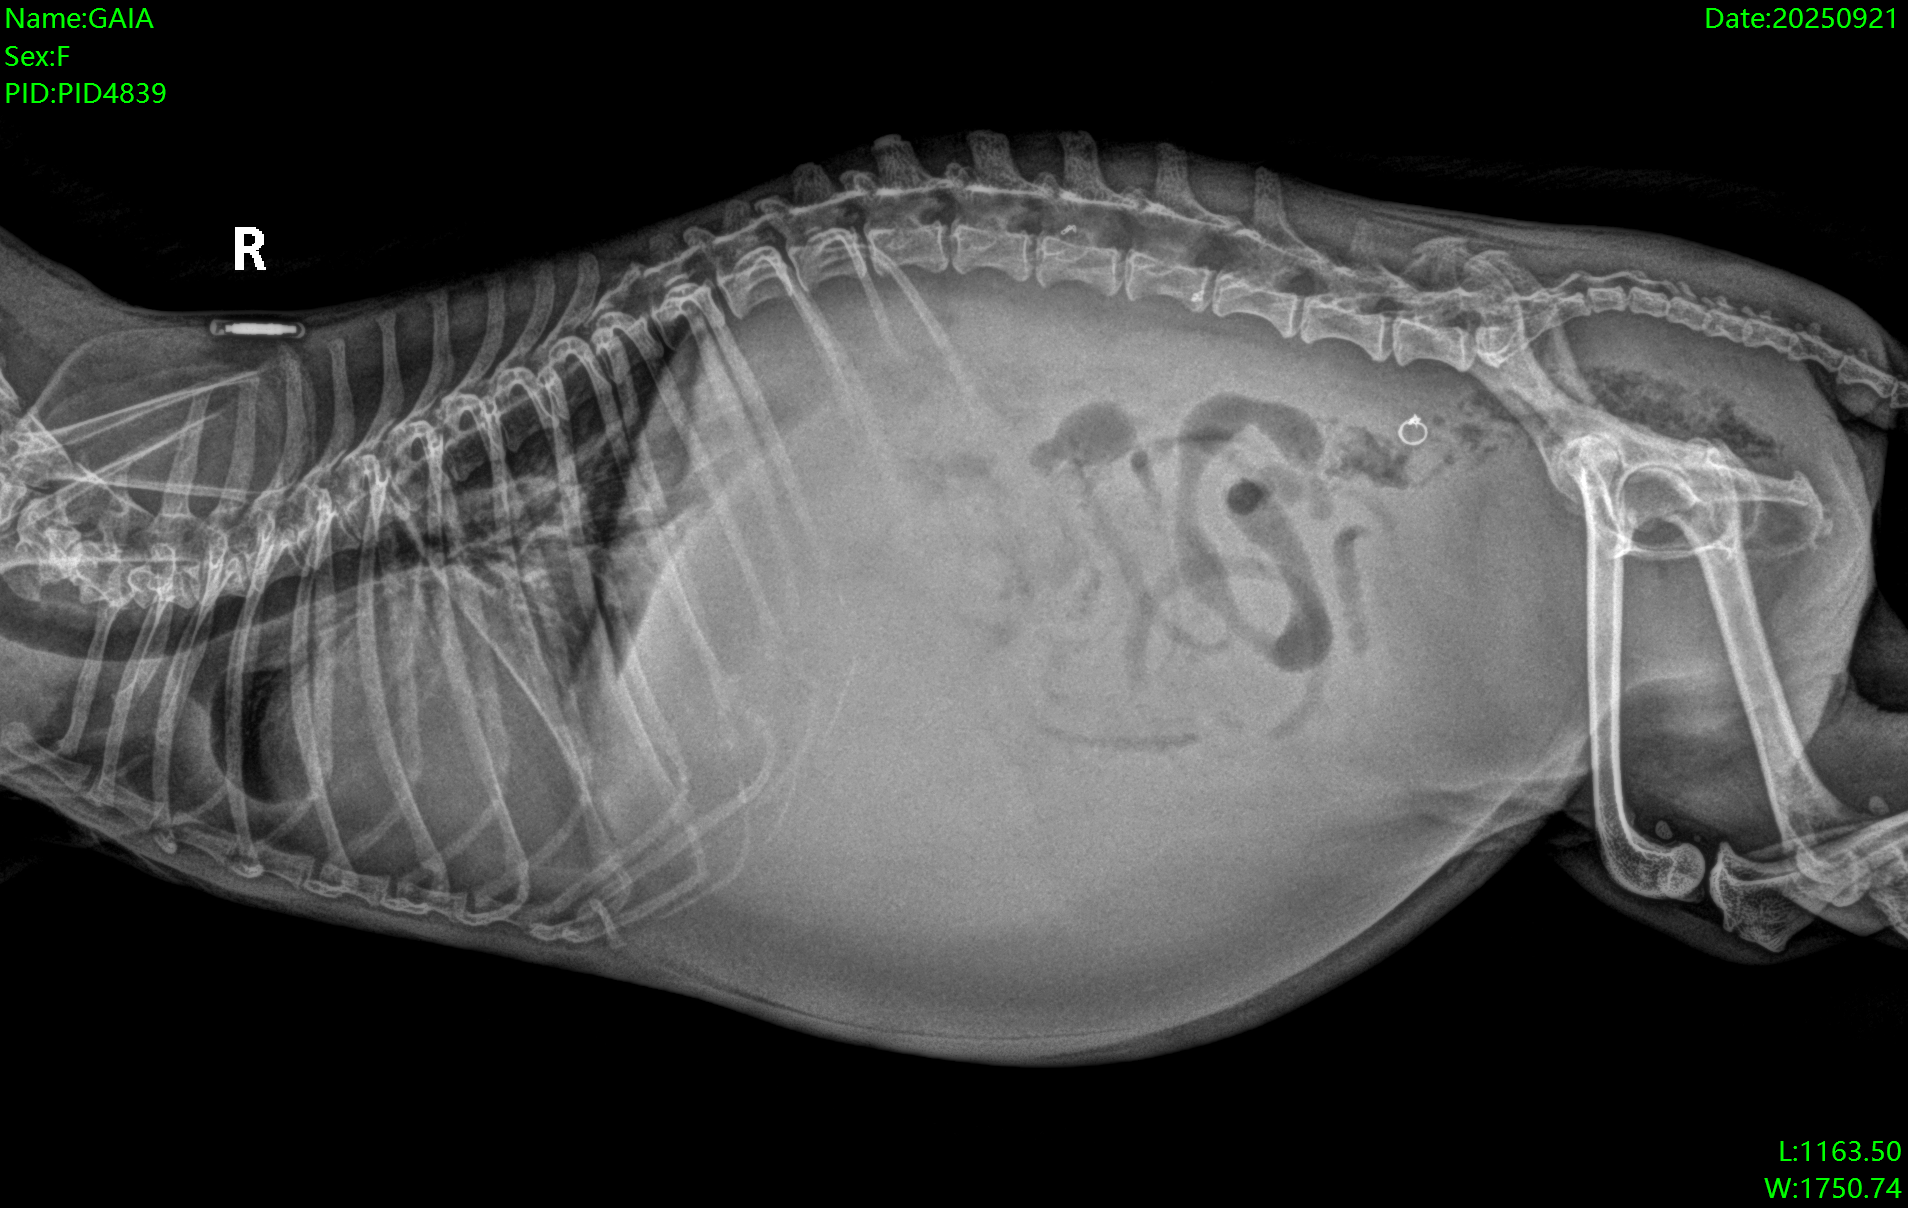

Hello everyone, Gaia is in need of medical assistance and we are trying to provide her with the best that we can. She’s seen three veterinary care providers now and we’ve been informed that she has a heart murmur. We were given medications to help with the condition. Unfortunately she has some liquid in her liver due to her cardiovascular condition. She is being treated and monitored at the veterinary. Please donate what you can or share the post. She is loved by many and has been around the family for various years now. Gaia and Sam are best friends and I wish for them to be able to spend more time together. She’s truly a light in our life and the best dog any family could ask for. Please help if you can.